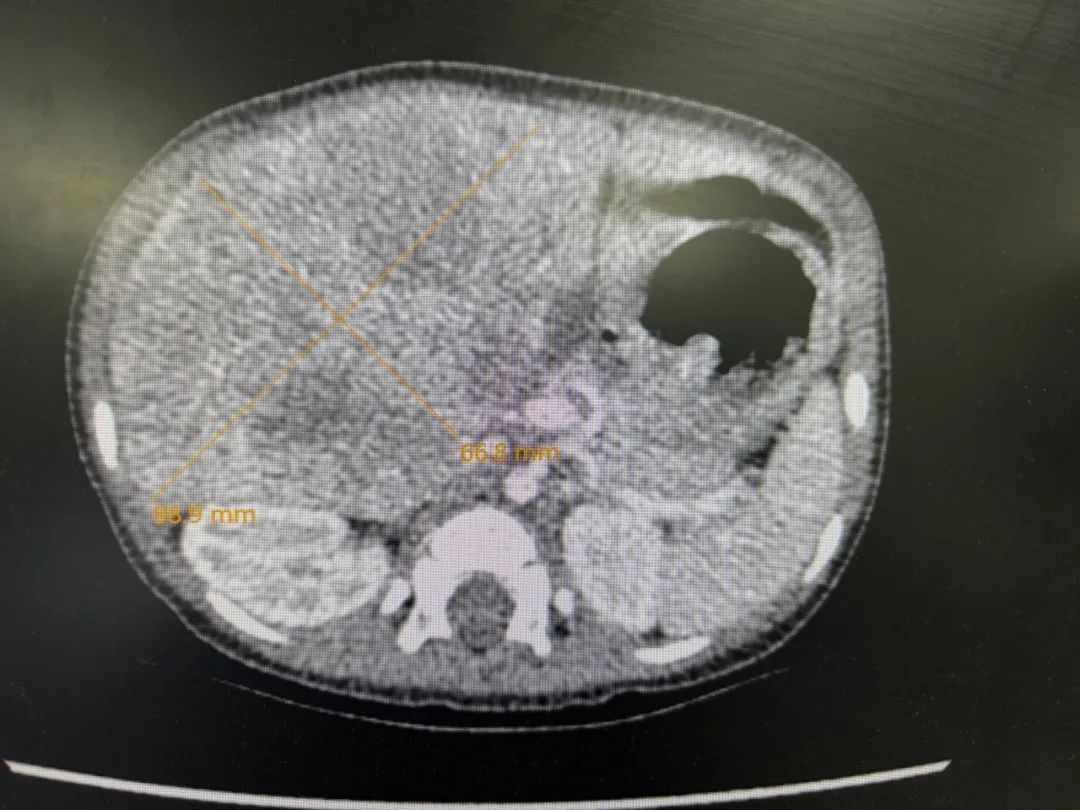

于是,爸爸妈妈带着妍妍找到武玉睿主任,在完善了各项检查后,基本可以明确,是肝母细胞瘤,最大径线达8厘米。肿瘤主要侵犯了肝第5段,6段和7、8段也有部分侵犯,肿瘤不止严重压迫正常肝组织和周围脏器,还与肝内的主要Glisson系统和肝静脉系统分界不清,如果贸然手术,要么需要扩大切除,这样就会丢失更多的肝组织;要么就不容易切干净肿瘤,因为初发肿瘤往往与肝内管道界限不清,强行手术的话肝内管道壁上容易残存瘤细胞,而且在肿瘤周围还有可能存在检查不出来的微小卫星灶,这都会增加术后复发的风险。经过权衡,武玉睿主任建议先给妍妍穿刺活检后做化疗,这样既可使瘤体缩小,又能使肿瘤建立假包膜,下次手术的时候,肿瘤与正常组织之间会有一个潜在间隙。而且化疗后,肿瘤周围可能存在的微小卫星灶一般也就被消灭掉了,所以化疗后再手术,肿瘤切除应该更彻底,复发率更低。经过了三轮的新辅助化疗,妍妍肝脏上的肿瘤比之前小了不少,于是,武玉睿主任决定给妍妍做根治手术。

化疗前